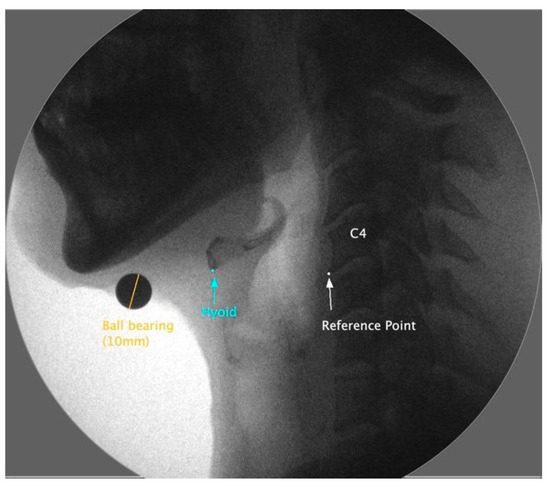

2.2. VFSS

2.4.1. Hyoid Bone Displacement

2.4.3. Laryngeal Excursion